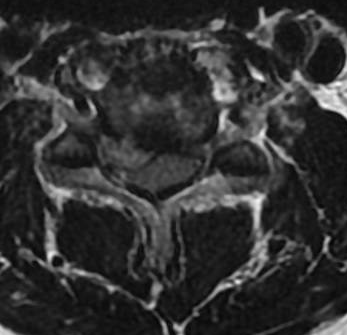

Update on the cervical epidural abscess case: Successful partial C4 corpectomy led to significant neurological recovery. Abscess was more phlegmon than liquid. Used fibular allograft for stability.